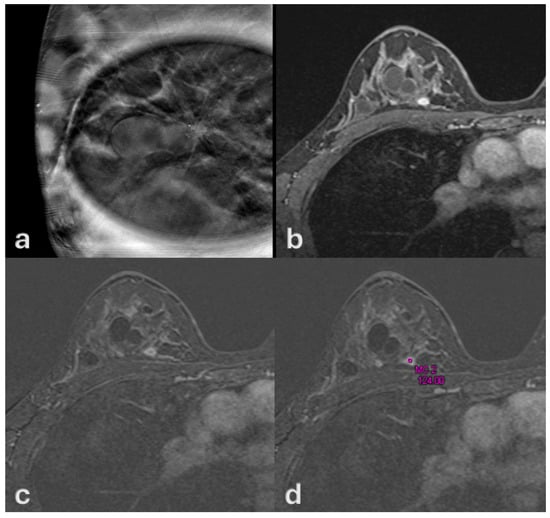

3. Results